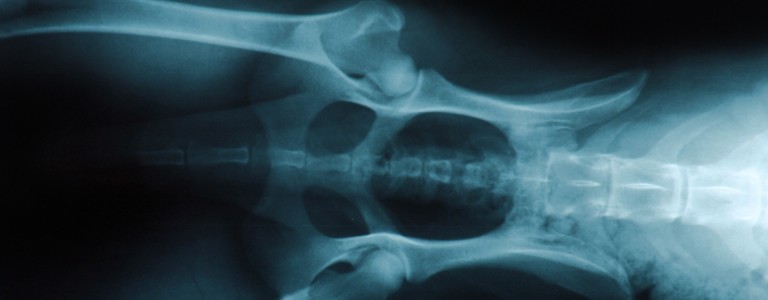

Si vous suspectez que votre chien souffre d'arthrose, un vétérinaire pourra en confirmer le diagnostic grâce à votre description des symptômes, un examen clinique complet et des examens d’imagerie.

Un diagnostic précoce permet de mieux gérer la maladie et d’en limiter les conséquences et la progression.